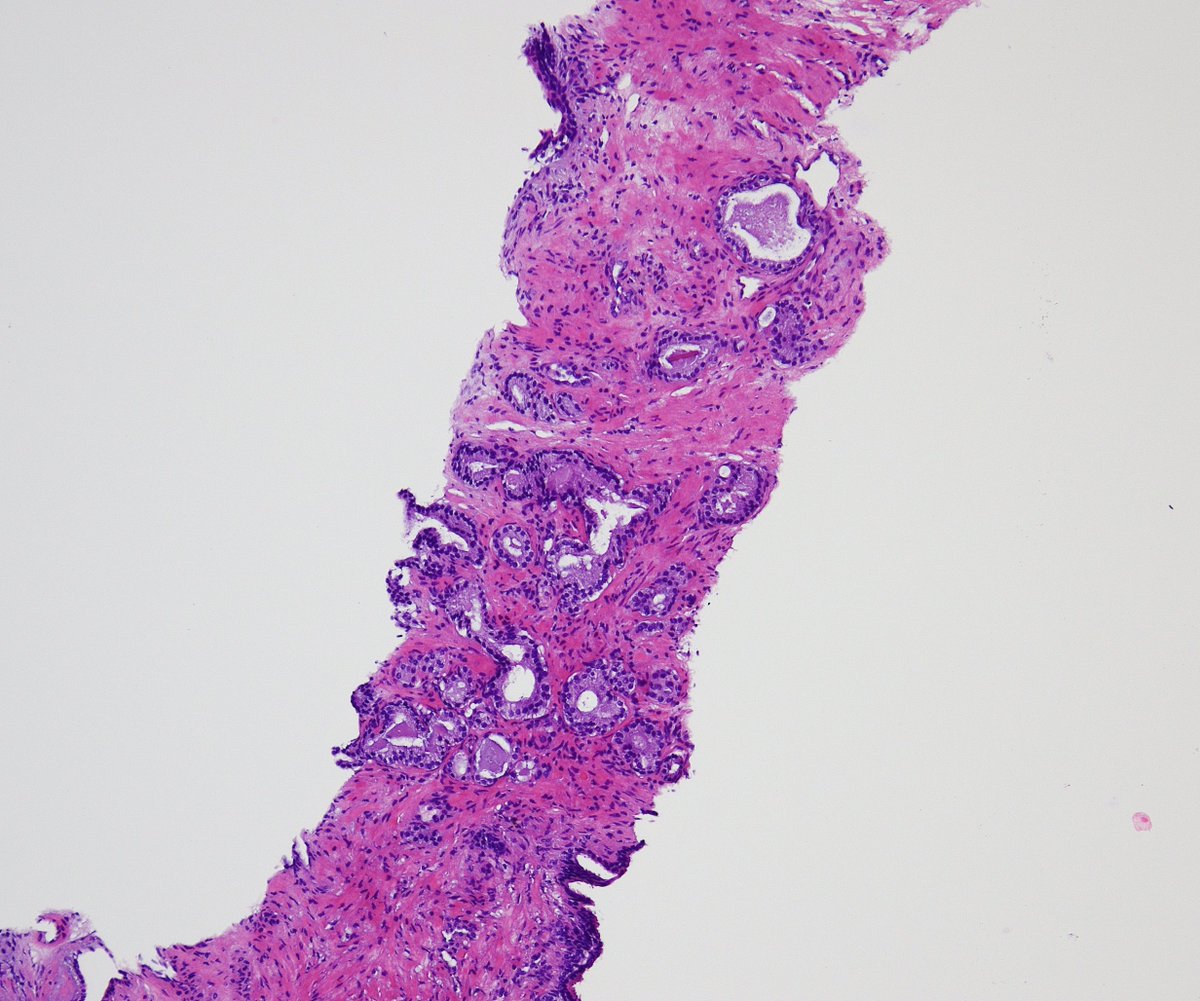

HER2 interpretation is increasingly complex—with evolving definitions come real challenges, especially reproducibility. We’ll cover navigating HER2-low & ultralow in a clinically meaningful way.